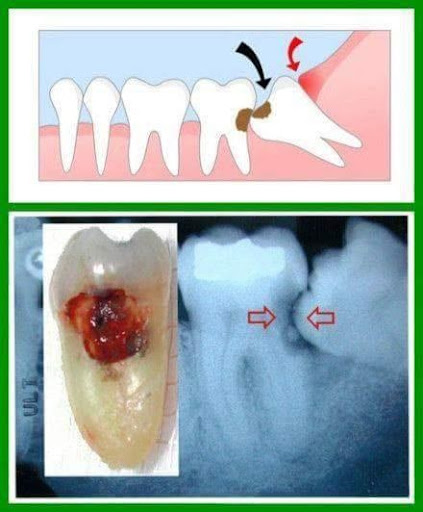

Nhắc tới nhổ răng thì ai cũng sợ và đều không muốn vì nghĩ răng nhổ răng khôn ảnh hưởng tới thần kinh rất nguy hiểm. Tuy nhiên, nhổ răng khôn thực ra không phải muốn hay không, mà là một chỉ định y khoa bởi vì răng khôn mọc sau cùng sát vách xương hàm, cạnh răng 7 thường không đủ khoảng trống để mọc dẫn đến mọc lệch, mọc kẹt. Các biến chứng răng khôn gây ra gồm: Đau nhức dai dẳng nhiều lần, sưng tấy có mủ nặng hơn dẫn đến viêm mô tế bào, gây sâu phải nhổ luôn cả răng 7.

Nhổ răng cũng giống như các phẫu thuật y khoa thường quy nên đau là điều không thể tránh khỏi, tuy nhiên nó nằm ở mức độ ít hay nhiều. Việc nhổ răng khôn hàm dưới thường gây đau và sưng hơn hàm trên do răng hàm dưới mọc theo nhiều tư thế khác nhau, có hình dạng kỳ quái, nằm gần hệ thống thần kinh mạch máu và xương hàm dưới cứng chắc hơn xương hàm trên nên khi nhổ răng hàm dưới sẽ khó hơn răng hàm trên đặc biệt các nguy cơ về nén xương.

Ngoài ra, với những ca răng khôn khó đòi hỏi kĩ thuật, thời gian lâu hơn, các bác sĩ còn phải tách lợi, mở xương ổ răng, chia cắt răng khôn thành từng mảnh nhỏ gắp ra ngoài nên không thể tránh khỏi sang chấn dẫn tới đau, sưng và chảy máu.